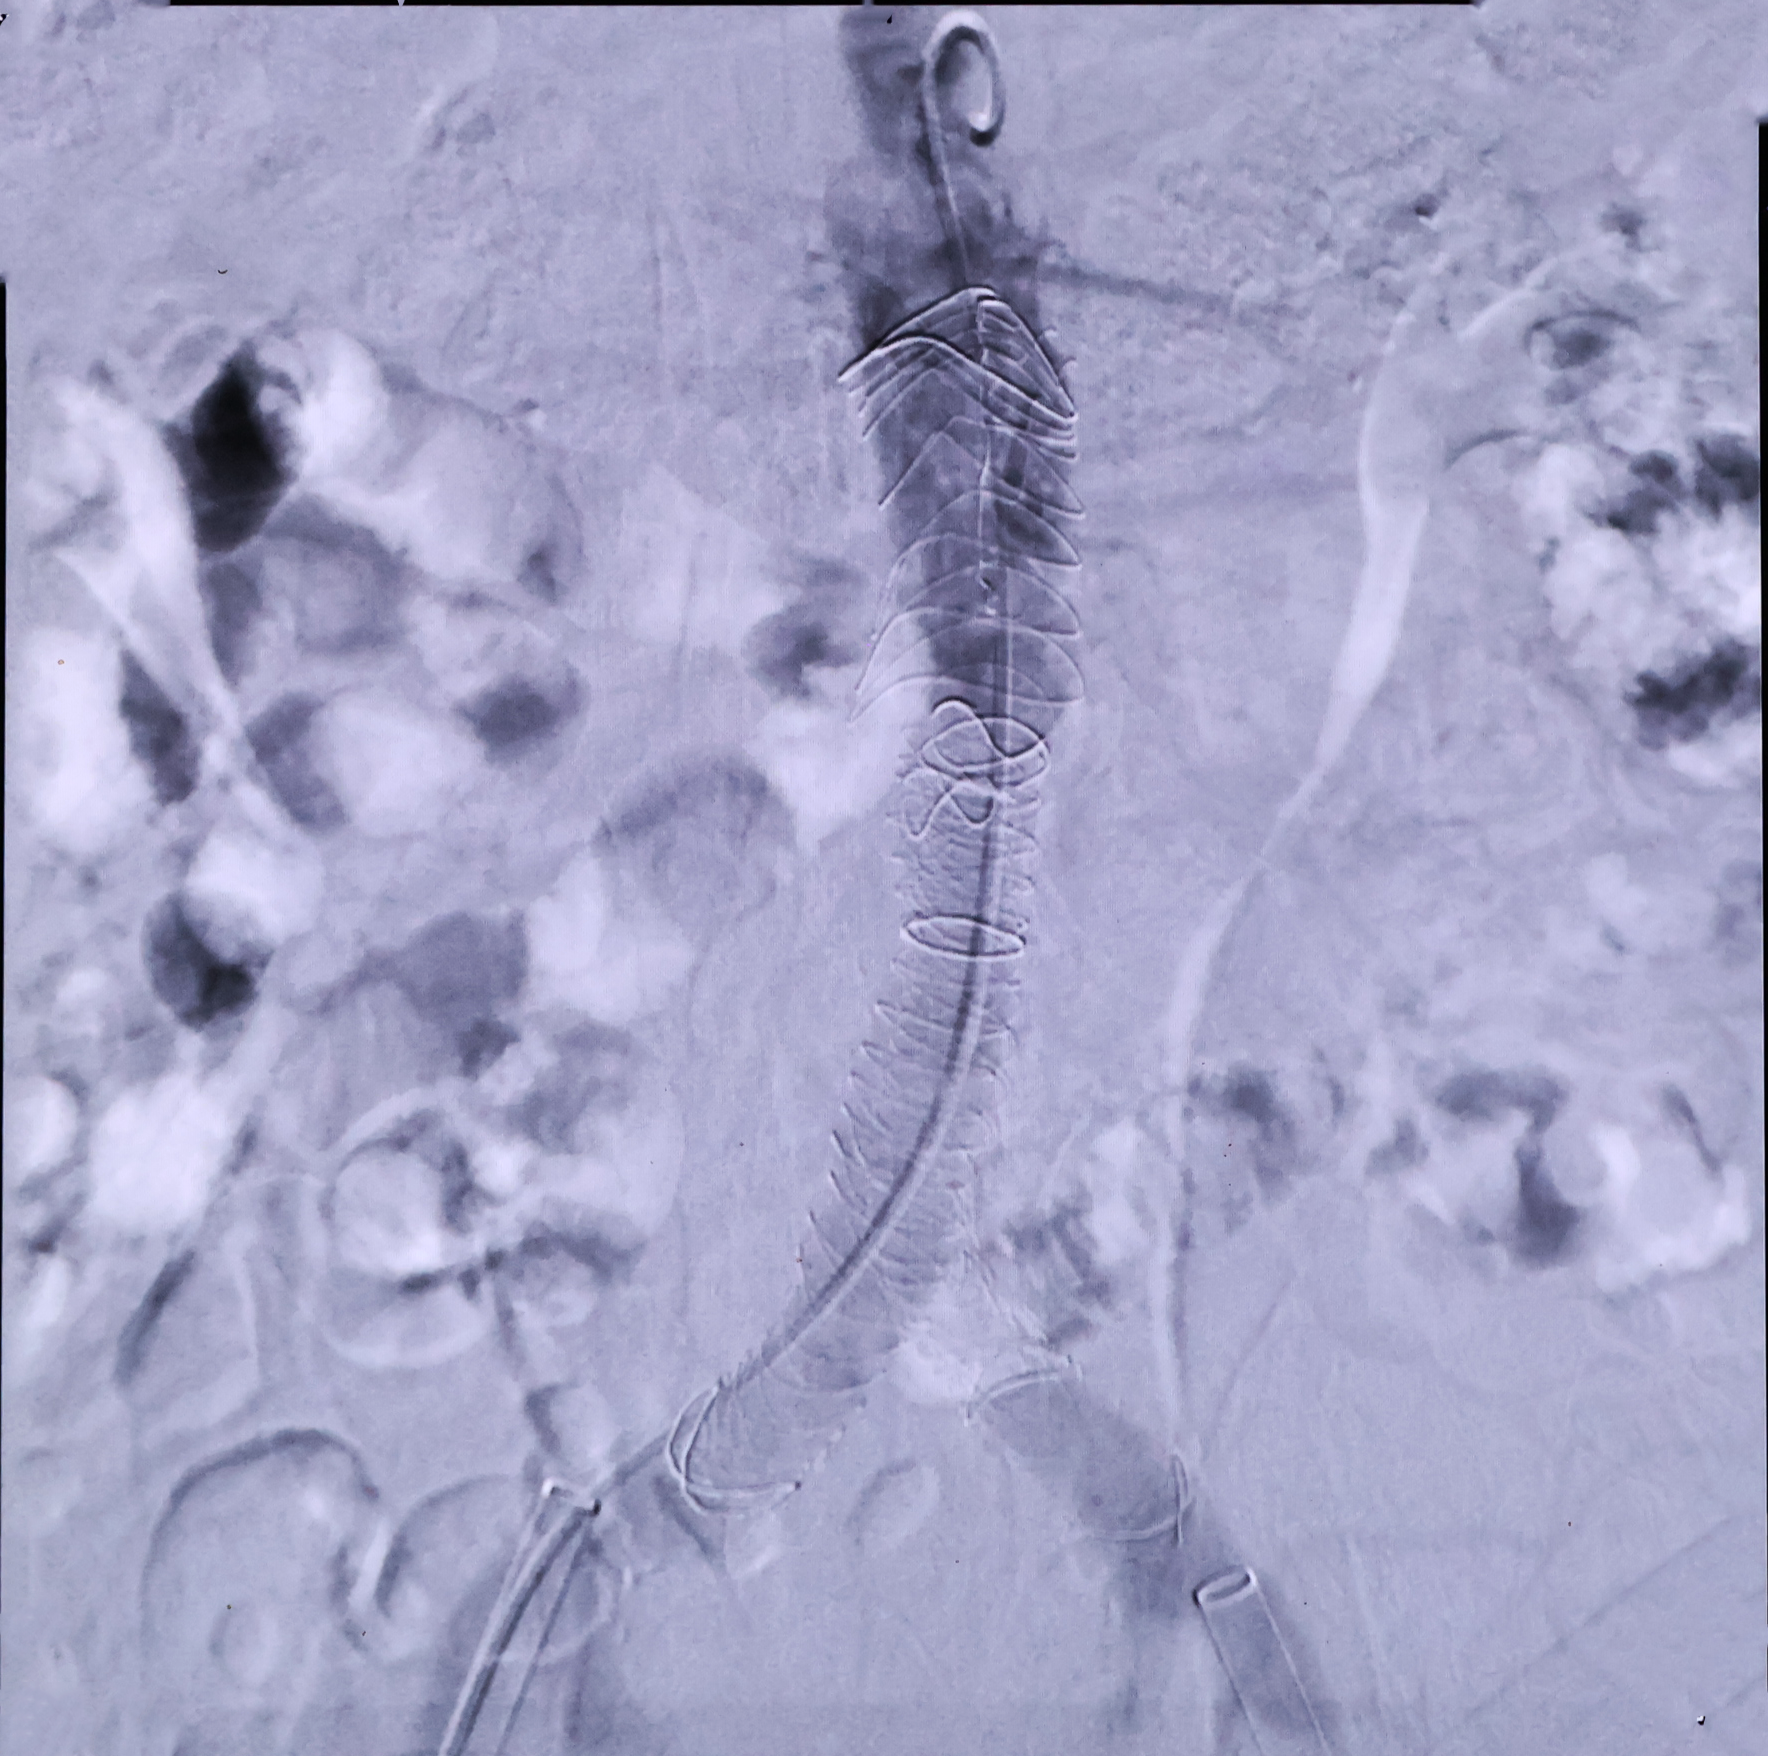

Endoprótesis vascular trimodular con boca de pez. permitiendo fijación transrenal activa con sistema de liberación de bajo perfil (18 Fr) para el tratamiento y reparación de aneurismas aorto abdominales estándar y complejos, que ofrece un diseño flexible y con alta adaptabilidad al vaso, debido a la conformación de sus materiales: poliéster/nitinol, en combinación con una estructura mixta (tecnología Halo); haciéndola adecuada inclusive para zonas de apoyo proximal y/o distal que presenta un ángulo considerable.

* Debido a su diseño circular (MB) y helicoidal (CL), con tecnología Halo, permite al sistema tener alta flexibilidad, resistencia y adaptabilidad a las tortuosidades naturales de los vasos, mantienendo el tamaño luminal incluso en anatomías extremadamente tortuosas.

*  Marcadores radiopacos de tantalio posicionados en el cuerpo y piernas del sistema, permitiendo un posicionamiento preciso debido a su alta visibilidad.